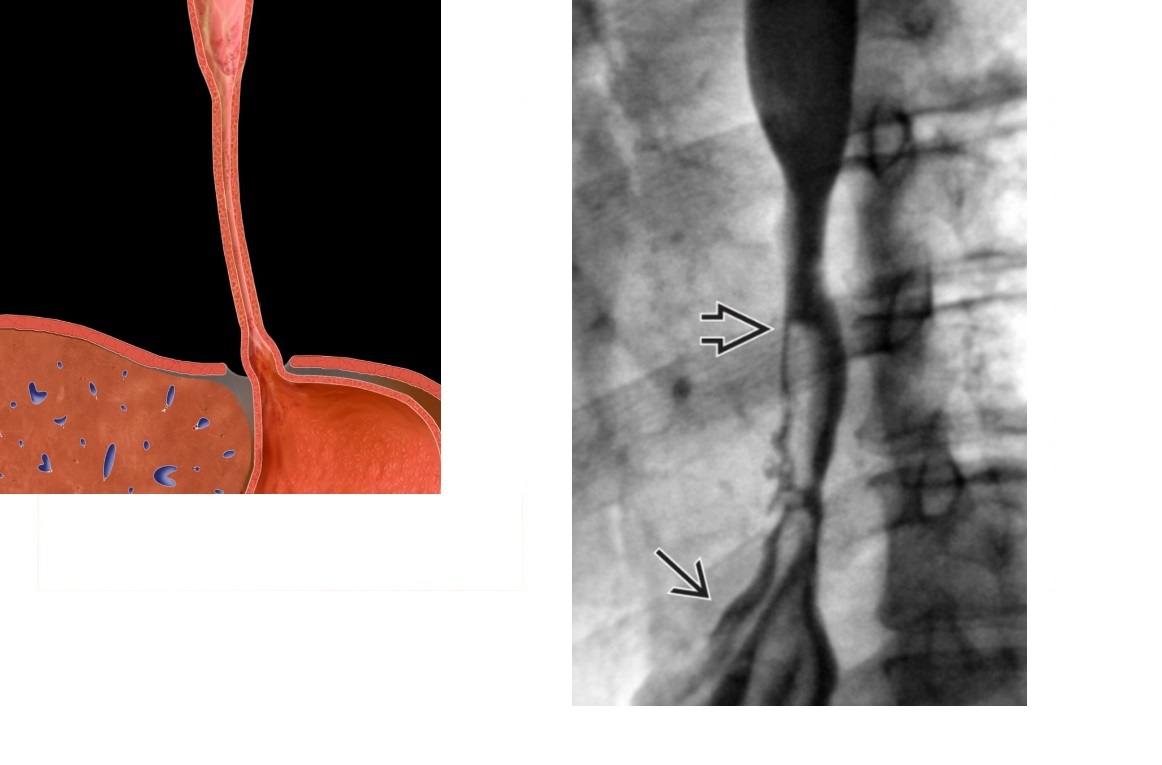

Epiphrenic diverticulum

Large saccular outpouching just above the diaphragm, right side

Can be mistaken for paraesophageal hernia - usually in on the left

associated with dysmotility disorders